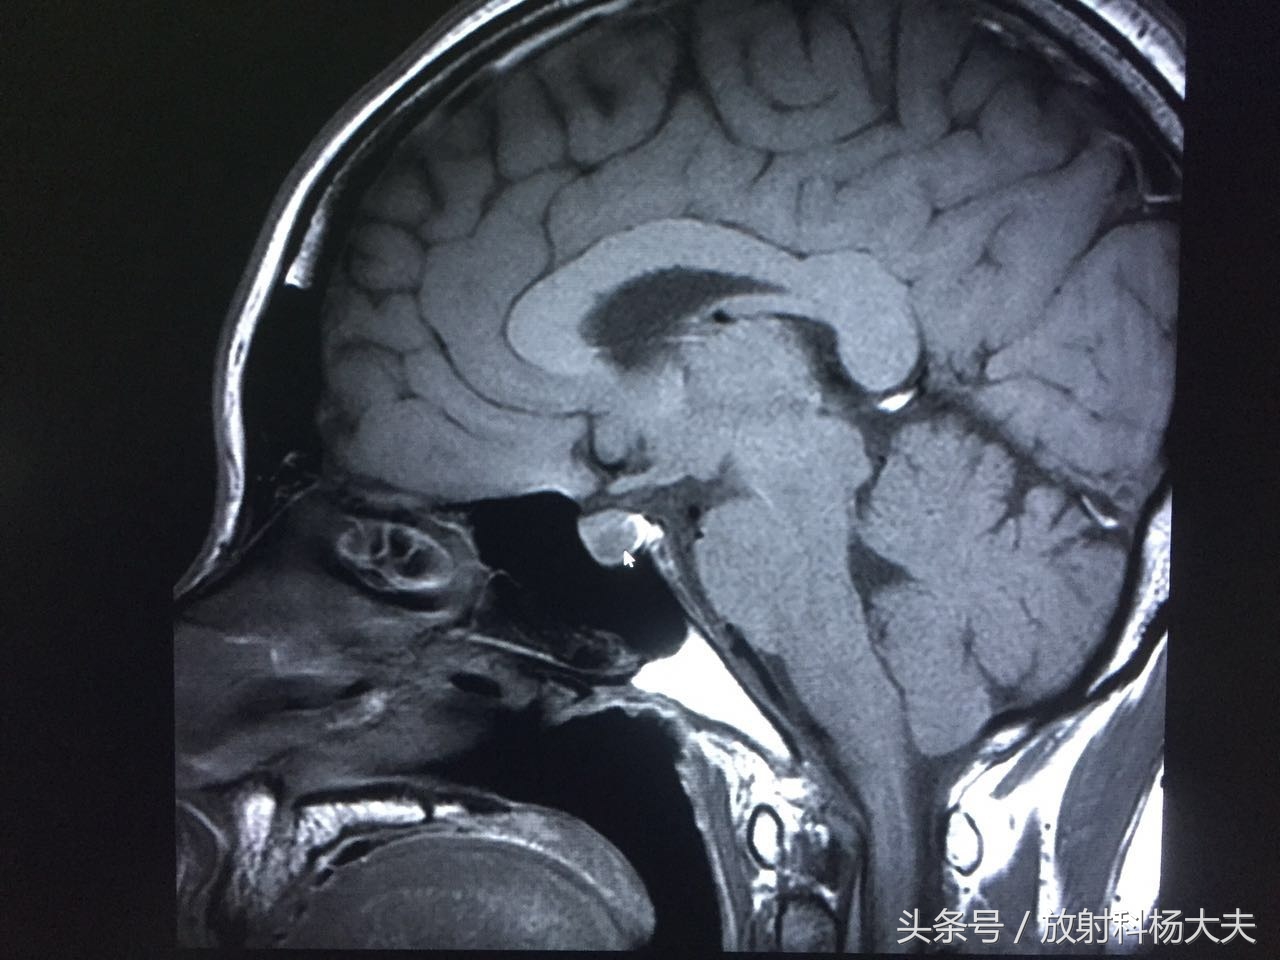

图像出来了,我们可看到垂体内的异常信号(短箭头所指地方),呈长T1混杂T2信号。

T2WI白箭所示为垂体,这个器官很小,但很重要

T1WI

动态增强扫描可见延迟强化,其延迟期扫描强化程度仍低于周围正常腺体。余垂体强化均匀。

箭头所示的为垂体的瘤子